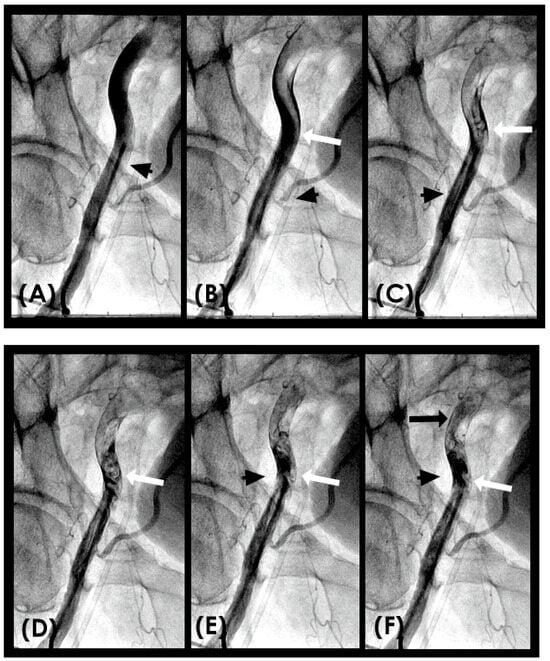

Conversely, in arteries affected by calcification, the vessel’s capacity to expand and contract becomes markedly compromised. The inability of the stiffened arterial wall to absorb the energy of the waves results in heightening the risk of endothelial microtears and further structural damage to the arterial wall (Figure 10) [26]. This phenomenon is particularly pronounced at the interface between calcified and non-calcified segments, which accounts for the frequent occurrence of new in-stent restenosis at the junction between the stent’s distal end and the arterial wall [27].

Additionally, this process elucidates the mechanism driving plaque cover rupture, which often arises at the junction between the plaque and adjacent normal tissue due to the impact of pressure waves on the mechanically unequal interface. As arterial stiffening progresses with calcification, it impedes the retrograde propagation of pressure waves [28]. This underscores the beneficial role of stenting in mitigating retrograde pressure wave effects on the new stent-scaffolded arterial wall. (Figure 11A–H).

CLINICAL APPLICATIONS Beneficial Effect of Stenting. When a patient receives a stent, the technical goal is to deploy a stent with optimal expansion of the lumen and well apposition of the struts to the arterial wall. The fluid mechanics and acoustics goals are to develop a laminar antegrade flow during diastole, with no reversed flow, and with minimal boundary layers due to resistance from the metallic stent scaffold (Figure 11A–H). This restoration of laminar flow reduces the risk of both early thrombosis and late restenosis. The reason why there is no pressure wave reflection from a water hammer event is because the blood pressure is very well controlled during PCI, and the stented segment of the artery breaks the undulating movement of the arterial wall from pressure wave [42].

From a fluid mechanics perspective, the beneficial mechanism of stenting should not be merely described as opening a flow channel to the distal segment of the coronary artery. Instead, it is more accurately characterized as restoring laminar flow within the coronary artery and mitigating retrograde pressure waves associated with water hammer phenomena. This refined understanding extends the concept of beneficial mechanisms to include plain balloon angioplasty (POBA) and drug-coated balloon angioplasty (DCB) [43].